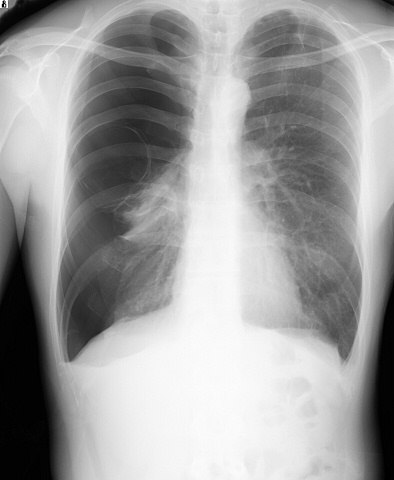

X-P

気胸